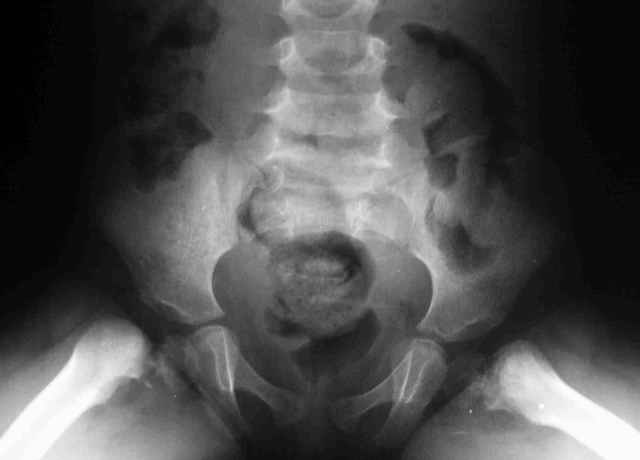

Дорогие коллеги,Нужен совет.Девочка 3 лет -врожденная двусторонняя кокса вара и как водится ограничено отведение и ротационные движения и *матросская* походка в развалочку.

Спасибо за комментарии, Врожденная кокса вара может рассматриваться как вариант фокального дефицита проксимального отдела бедра, но как-то не складывается у меня впечатление о дисплазии впадин и дефекте проксимального бедра - сформирована вертельная область, хотя шейка бедра практически не видна,коэффициент покрытия проксимального эпифиза нормален. Что обращает на себя внимание - это расширенные и вертикально ориентированные зоны роста( угол Хильгенрейнера около 90 градусов и формирование остеофита по нижнему контуру ростковой зоны.